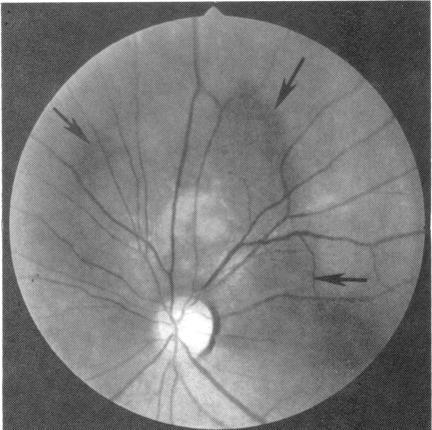

A 52-year-old woman was found to have a small juxtapapillary pigmented lesion in the choroid of the left eye. This lesion remained clinically stationary for one year, but subsequent growth prompted enucleation of the eye. The tumour was diagnosed histologically as a choroidal malignant melanoma of mixed cell type. Approximately 52 months later the patient developed proptosis of the contralateral (right) eye. Orbital ultrasonography showed a large mass in the right orbit, which was confirmed by needle biopsy to be a melanoma. In addition the patient was found to have metastatic melanoma to the choroid, right lower eyelid area, and liver. The development of simultaneous orbital, choroidal, and eyelid metastases from a contralateral choroidal melanoma is of ophthalmic interest and appears to be unique.

摘要